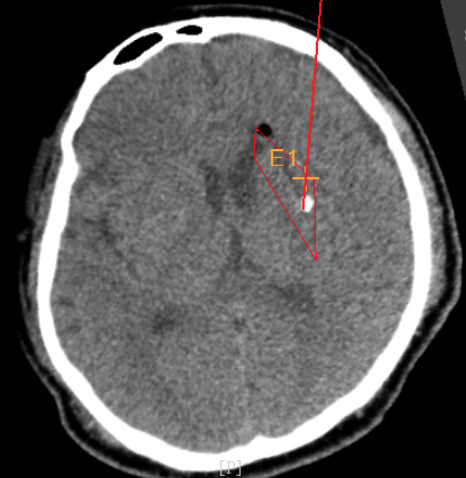

術(shù)前CT:血腫已經(jīng)液化,但仍有占位效應(yīng)